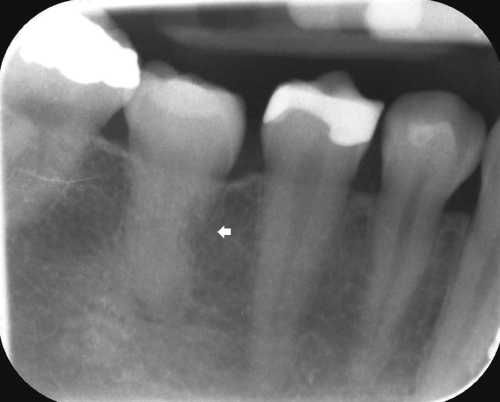

Дальше идёт проектирование будущей ротовой полости. Обычно у нас уже есть на этот момент снимки КТ на аппарате достаточной точности, где видно и все интересующие ткани, и нервные каналы, сосуды, и все имеющиеся во рту конструкции. Ортопед (или терапевт, в зависимости от характера операции) вместе с хирургом проектирует, что у пациента будет во рту позже.